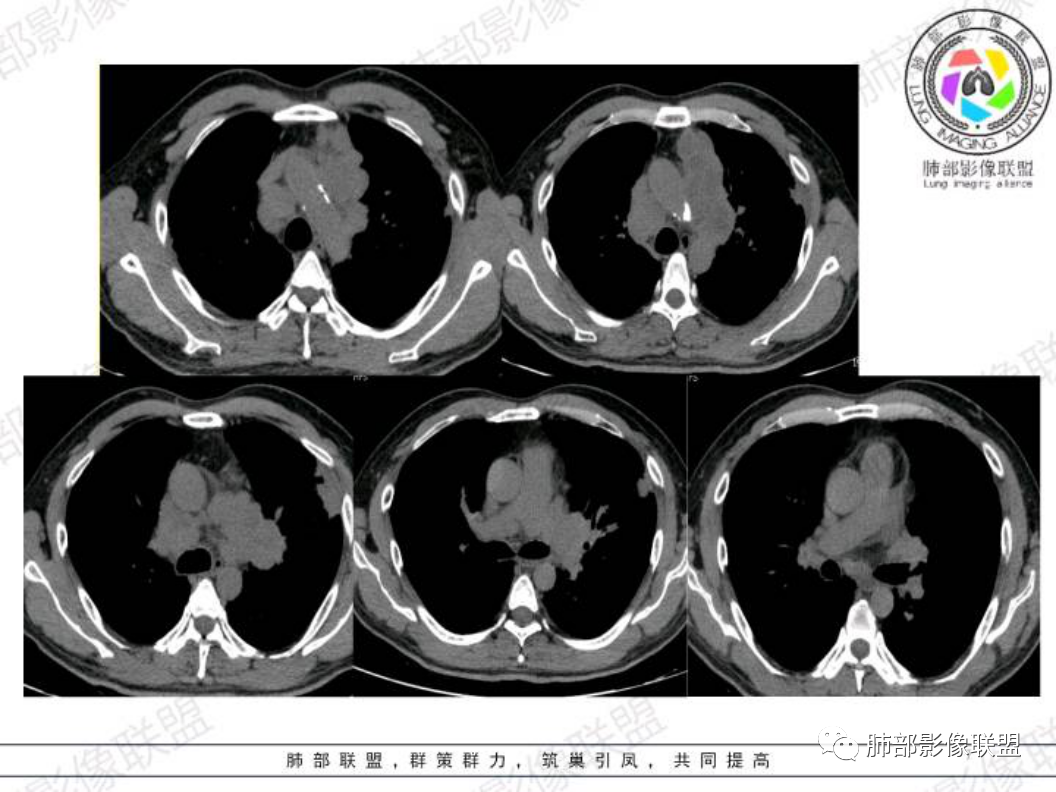

左肺上叶胸膜下实性结节,形态不规则,边缘毛糙,平行胸膜,近段支气管在病灶内堵塞,远端与胸壁相贴,左侧前纵隔多发肿大淋巴结融合,伴左肺门淋巴结肿大。

左肺上叶胸膜下不规则结节影,平行胸膜长轴,毛刺,支气管进入截断,胸膜糊墙,纵隔多组淋巴结肿大融合,平扫部分淋巴结密度不均。考虑恶性,小。鉴别结核。

中老年男性。糖尿病多年。考虑恶性,左上肺胸膜下病灶+左肺门纵隔多发肿大淋巴结,而且坏死融合,小细胞癌?其他?需要增强扫描。

老年男性,糖尿病,CT左肺上叶胸膜下实性结节,有一定的膨胀性生长形态不规则,边缘毛糙,平行胸膜,左侧前纵隔及肺门多发肿大淋巴结融合,考虑恶性病变,小细胞癌或低分化腺癌伴转移可能。

中年男性,咳嗽咳痰一个月,有糖尿病史,肺纤维化病史,左肺门不规则肿块,边缘膨隆,有分叶,内有多灶性坏死,支气管截断阻塞,远端靠近胸膜下斑片实变影,纵隔淋巴结肿大,考虑恶性,小细胞肺癌可能性大,鉴别肺结核。

纵隔淋巴结肿大,融合,坏死,不是小细胞的冰冻纵隔,低分化腺癌这种表现最常见,偶尔低分化鳞癌也可以。

胸膜下是原发灶,胸膜下往纵隔走,有癌淋存在。

有增强的话,可以明确看到多个淋巴结轮廓和明显的坏死,大家应该都不会考虑小细胞了。

这种平扫都能看出明显的淋巴结坏死的纵隔转移,而且双侧纵隔淋巴结基本对称,就可以直接把小细胞pass掉了。

可惜没有增强扫描。小细胞肺癌的冰冻纵隔一般是患侧肺门向纵隔过度的,如果患者肺门没有冰冻,纵隔对称性的淋巴结肿大融合坏死,小细胞肺癌就想都不用想了。

在低分化腺癌伴有神经内分泌分化倾向的时候,NSE可以增高,这个病人CgA灶性阳性,可能伴有神经内分泌分化。